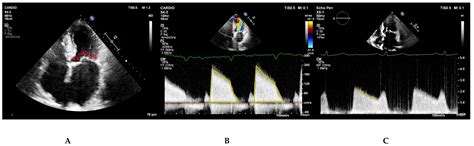

When interpreting the results of a *mitral stenosis echo*, cardiologists look for several key indicators:

Valve Morphology: The shape and structure of the mitral valve are examined to determine the extent of narrowing and any signs of calcification or thickening.

Valve Area: The area of the mitral valve opening is measured. A normal valve area is typically around 4-6 cm². In mitral stenosis, this area is significantly reduced, often to less than 2 cm².

Pressure Gradient: The pressure difference between the left atrium and left ventricle is measured. A higher gradient indicates more severe stenosis.

Flow Velocity: The speed of blood flow through the mitral valve is assessed. Higher velocities suggest more severe narrowing.

Left Atrial Size: The size of the left atrium is evaluated. In mitral stenosis, the left atrium often enlarges due to the increased pressure.

Pulmonary Artery Pressure: Elevated pulmonary artery pressure can indicate the presence of pulmonary hypertension, a common complication of mitral stenosis.